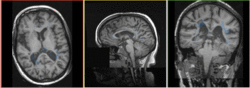

Slicer Registration Use Case Exampe: Intra-subject Brain MR FLAIR to MR T1

reference/fixed : T1 SPGR , 1x1x1 mm voxel size, sagittal, RAS orientation.

moving: T2 FLAIR 1.2x1.2x1.2 mm voxel size, sagittal, RAS orientation.

Registration Results

Registration Result: FLAIR + segmentation aligned with SPGR